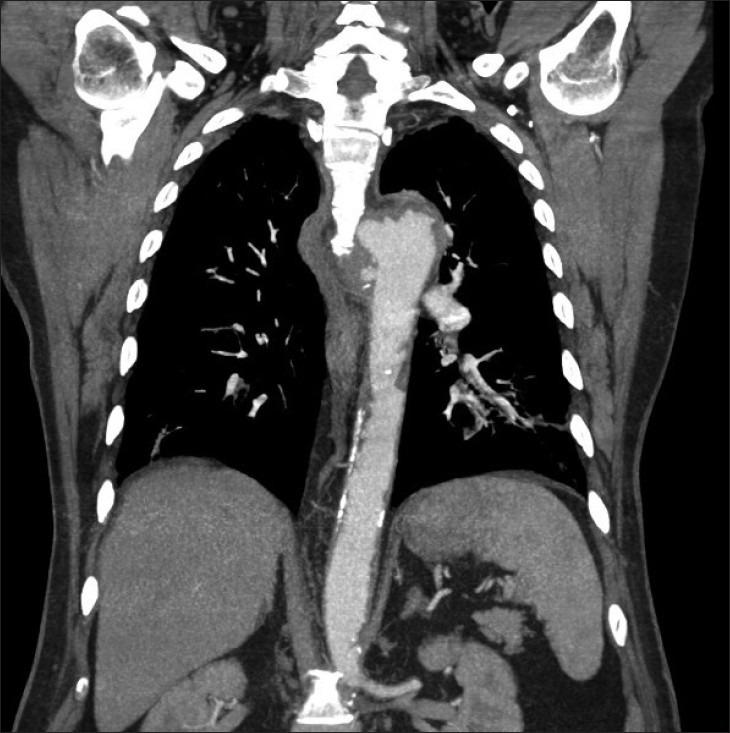

Aorto-esophageal fistula secondary to penetrating atherosclerotic ulcer.

Aorto-esophageal fistula (AEF) is a rare and life threatening condition, which can be rapidly fatal. More than half of such cases are secondary to aortic aneurysm rupture. There are only two previous reports describing AEF caused by penetrating atherosclerotic ulcer. We present multidetector computed tomography findings in a case of AEF secondary to penetrating atherosclerotic ulcer.

主动脉食管瘘(AEF)是一种罕见且危及生命的疾病,可迅速致命。超过半数的此类病例继发于主动脉瘤破裂。此前仅有两份报告描述了由穿透性动脉粥样硬化溃疡引起的AEF。我们报告了一例继发于穿透性动脉粥样硬化溃疡的AEF的多排螺旋计算机断层扫描结果。